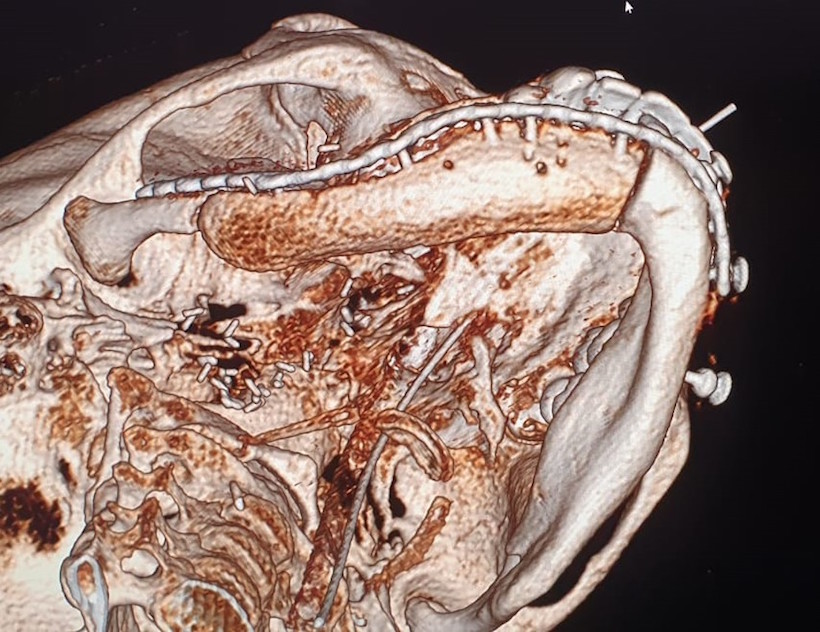

W okresie pooperacyjnym nie stwierdzono powikłań w gojeniu ran pooperacynych. W wykonanych badaniach tomografii komputerowej części twarzowej czaszki (Fig. 21.) oraz OPG (Fig. 22.) potwierdzono poprawność rekonstrukcji żuchwy oraz prawidłową pozycję jednoczasowo założonych implantów. Po upływie 6 miesięcy od wykonanego zabiegu chirurgicznego i pełnym zrośnięciem się kikutów żuchwy z płatem mikrochirurgicznym z talerza kości biodrowej oraz osteointegracji implantów zębowych z przenoszonym fragmentem kostnym w chorej planowane są dalsze etapy leczenia implantoprotetycznego.

Fig. 21. Odtworzony fragment trzonu, kąta i gałęzi żuchwy po stronie prawej na rekonstrukcjach 3D kontrolnego badania tomografii komputerowej